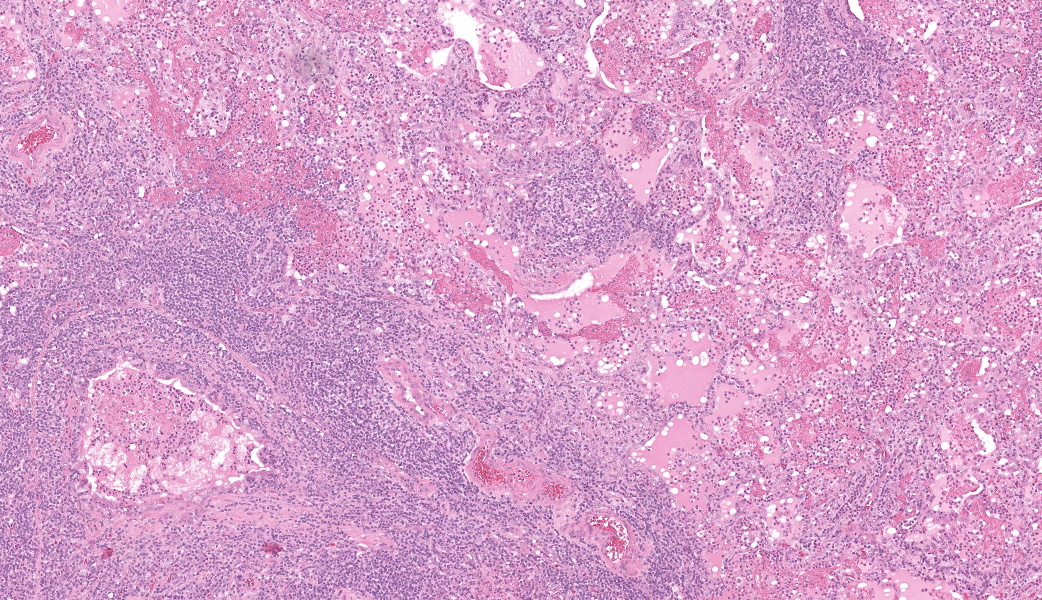

Camel; LungDescription Multifocally throughout the section, expanding the lamina propria of larger airways, multifocally invading the airway epithelium, expanding numerous alveolar septae and infiltrating into interlobular septae and the pleural space, there is a densely cellular lymphoid neoplasm. The neoplasm is made up of sheets and rows of closely packed round cells supported by a fine pre-existing fibrous stroma. The neoplastic cells contain nuclei 5-7µm in diameter and have indistinct cytoplasmic borders, scant amphophilic cytoplasm, round to ovoid paracentral nuclei with coarsely clumped chromatin with moderate numbers of cells possessing a single nucleolus. Throughout the neoplastic cells there is mild anisokaryosis and anisocytosis. Mitotic figures numbering 5 per 2.37mm2 with occasional bizarre mitoses. Multifocally the neoplastic cells closely surround and infiltrate the tunica media of small blood vessels. Numerous alveolar spaces are filled with eosinophilic fibrillar material (fibrin) admixed with abundant neutrophils and foamy macrophages, while others contain large amounts of homogenous eosinophilic material (edema). Multifocally some alveolar spaces are expanded and ruptured (emphysema). Bronchioles contain moderate numbers of neutrophils and macrophages admixed with strands of hypereosinophilic fibrillar material (fibrin) with neutrophils transmigrating across the respiratory epithelium. There is occasional loss of type I pneumocytes with replacement by type II pneumocytes.

Lung and Lymph node; B-cell lymphomaLung; bronchopneumonia, fibrinosuppurative, multifocal, severe, subacute, with type II pneumocyte hyperplasia.

In this case, neoplastic cells were also found in the liver, spleen and heart of the camel. No neoplastic cells were found in the kidneys or in two sections of bone marrow (rib and sternum). The presence of atypical lymphocytes within the peripheral blood collected at the initial clinical examination greatly aided the diagnosis of lymphoma or leukemia in this case (Figure 1) and allowed the clinician to understand why this animal did not improve like the others in the herd once nutrition was improved. The neoplastic cells observed in the peripheral blood was suspected to be secondary to the lymphoma, given that no neoplastic cells were found within the bone marrow of the bones examined histopathologically. Leukemia is a feature of less than 20% of lymphomas in animals and is more commonly a feature of T-cell lymphomas.9 Leukemia is most likely observed when the lymphoma invades the bone marrow or spleen, the latter of which contained neoplastic cells in this case.9 In this case a B-cell phenotype was confirmed via immunohistochemistry (Figures 7-11).There are only a few reports in the literature describing lymphoma in dromedary camels. Similar to this case, the disease is typically reported in adult animals (>7 years) and has been reported in both male and female camels. Common clinical presentations include weight loss, anorexia, polyuria and polydipsia, with one report also describing peripheral lymphadenopathy and bilateral masses in the conjunctiva of one animal.3,4,6 Peripheral lymphocytosis, sometimes with significant atypia in circulating lymphocytes and lymphoblasts, has been reported occasionally but is not always a feature of the disease in dromedary camls.3,7

Histologically, lymphomas in dromedary camels are described as a highly cellular neoplasm often effacing the normal architecture of the tissues, made up of sheets of lymphoid cells with scant cytoplasm and distinct cell margins. There is some variability in the cellular morphology including anisocytosis and anisokaryosis, indistinct nucleoli to multiple nucleoli present and in one case multinucleated cells were observed.3,4,6